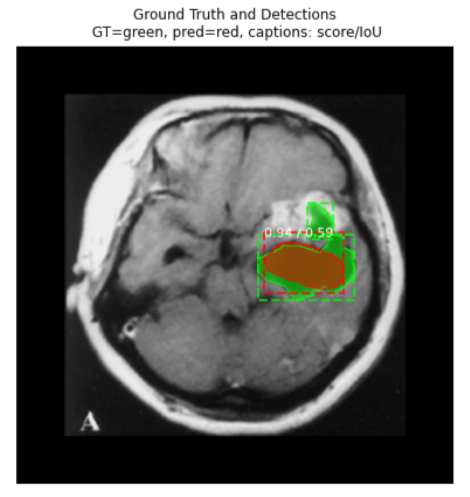

Test your model prediction on the validation set:

#Validation set

ind = 9

display_image(dataset_val, ind)

predict_and_plot_differences(dataset_val, ind)

As you can see we are getting pretty good accuracy.